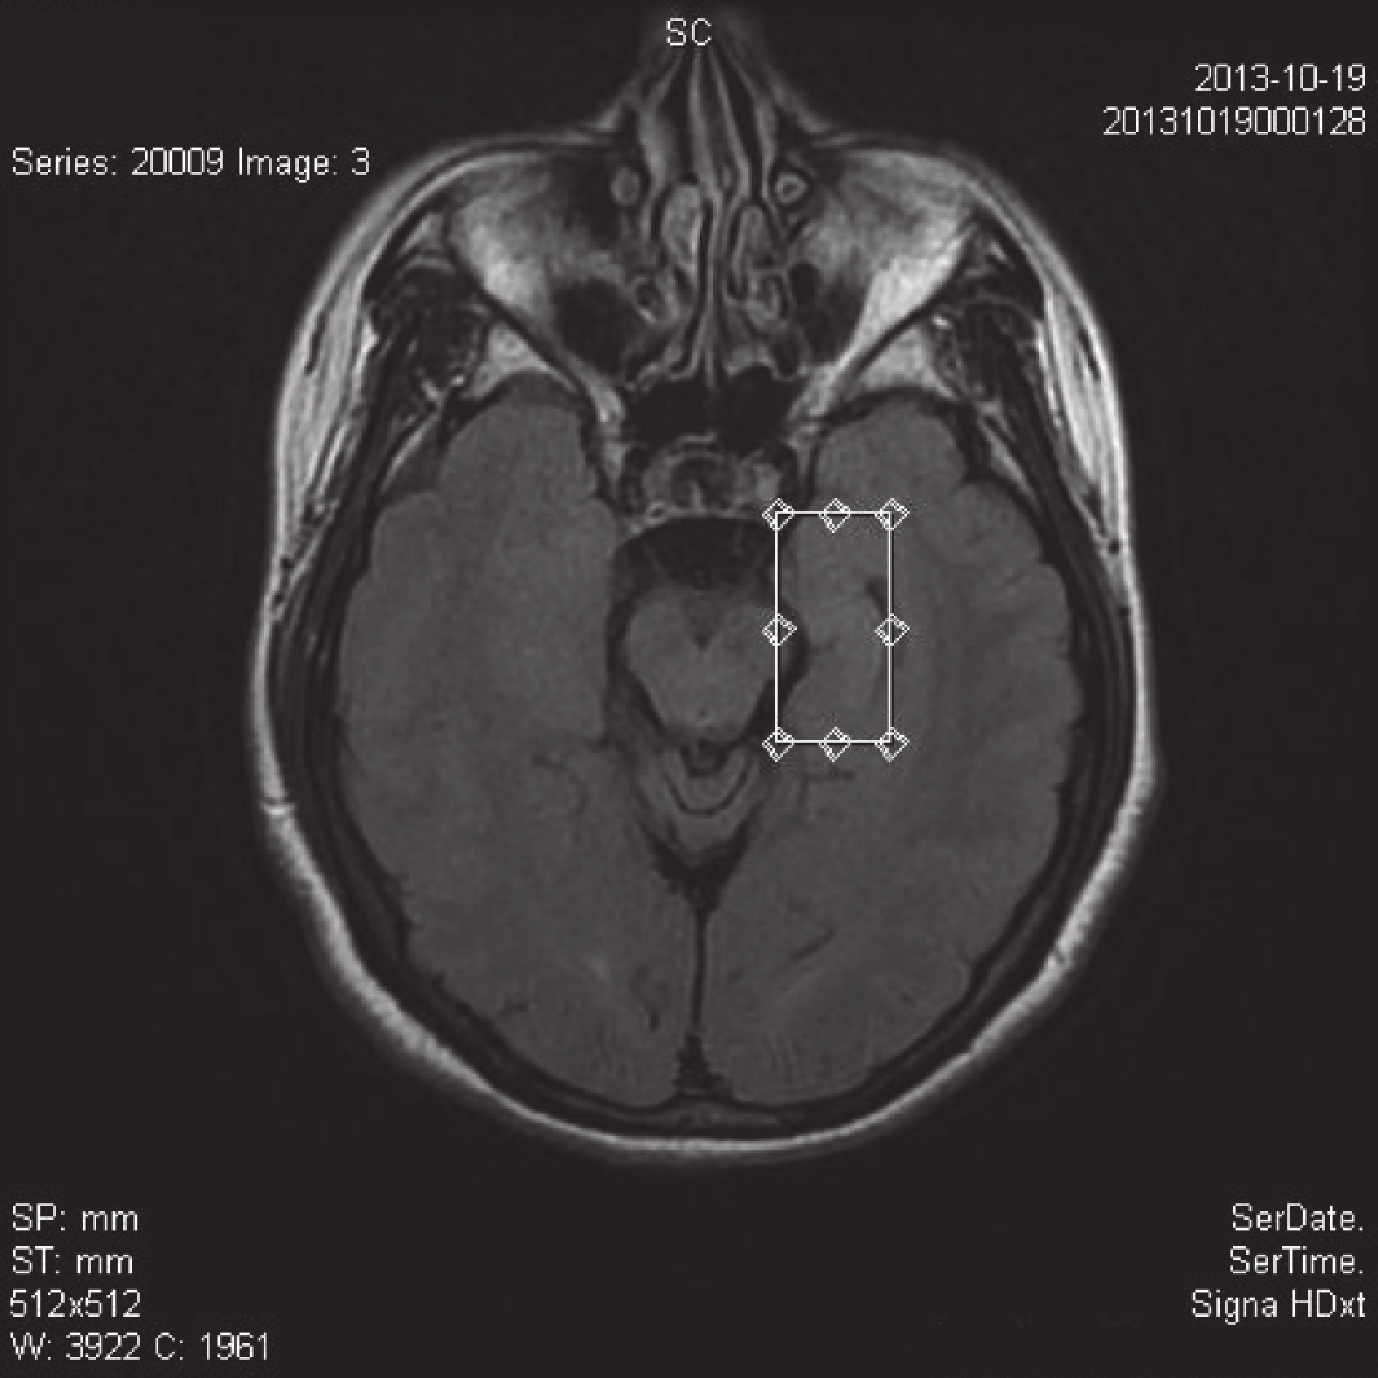

所有患者術前均行斷層掃描(CT)和核磁共振(MRI)檢查,CT 檢查均提示無明顯異常。MRI 檢查除了進行常規的 T1WI 和 T2WI 序列掃描外(圖 1),另外加行 FLAIR 序列掃描(圖 2)和雙側海馬 MRS 檢查(圖 3、4),均診斷為海馬硬化,其中左側海馬硬化 16 例,右側海馬硬化 26 例。海馬硬化 MRI 診斷標準包括:T1WI 顯示海馬體積縮小、側腦室顳角擴大、海馬區 T2WI 高信號以及 FLAIR 序列高信號,以及 MRS 檢查提示一側海馬 NAA/(Cr+Cho)<0.71 或者雙側海馬 NAA/(Cr+Cho) 差值>10%。

磁共振波譜(Magnetic resonance spectroscopy,MRS)是近年來應用于癲癇定位診斷的新技術,在中樞神經系統主要測定 NAA、Cho 和 Cr 三種化學成分。NAA 反映神經元數量,Cr 和 Cho 則主要反映膠質細胞數量。海馬硬化主要病理改變為海馬神經元細胞減少伴不同程度膠質增生。故其主要 MRS 表現為 NAA 峰降低和 Cr、Cho 峰升高[10]。目前國內外均以 NAA/(Cr+Cho) 值作為診斷標準,因 NAA/(Cr+Cho) 正常值國內尚無統一標準,一般將對照組 NAA/(Cr+Cho) 平均值下限 (0.68) 作為病變組 NAA/(Cr +Cho) 值降低的診斷標準,將雙側 NAA/(Cr+Cho) 差值>10% 作為判斷病變組 NAA/(Cr+Cho) 值降低嚴重側的診斷標準[11]。本組 42 例患者行 MRI 檢查時除了進行常規的 T1WI 和 T2WI 序列掃描外,另外加行 FLAIR 序列掃描和 MRS,均診斷為海馬硬化,其中左側海馬硬化 16 例,右側海馬硬化 26 例。